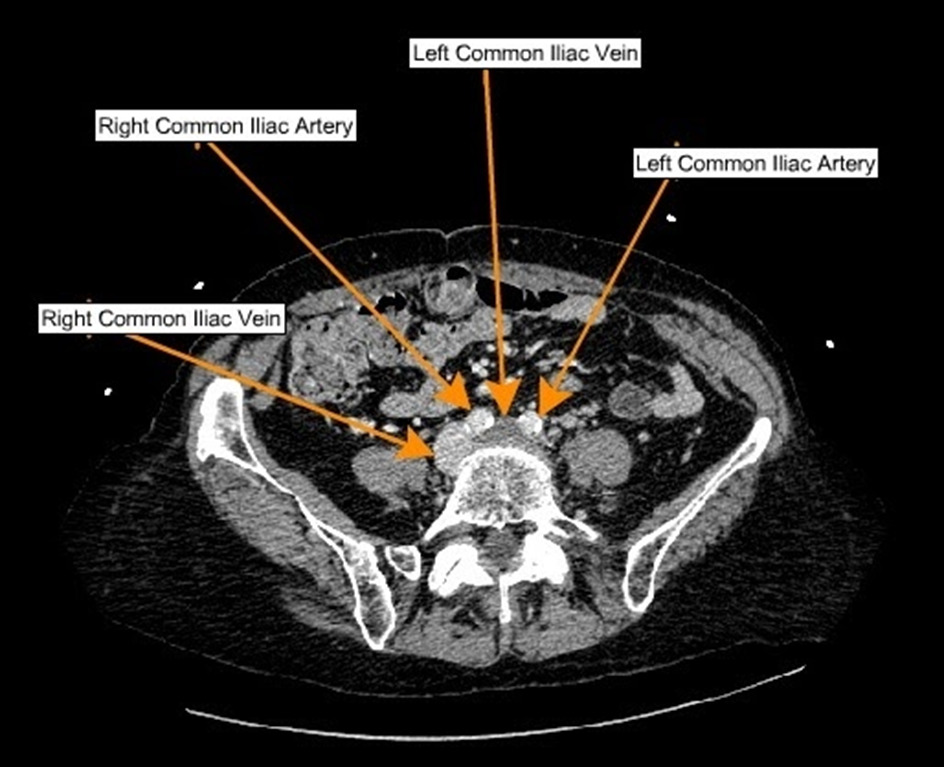

Physical examination included heart rate of 119 beats/min, blood pressure of 136/78 mmHg, and oxygen saturation of 95% on ambient air. The left lower extremity was markedly erythematous and swollen without calf tenderness (Figure 1). The sole of her left foot appeared mildly cyanotic. Bilateral varicose veins were present, and peripheral pulses were normal. A complete blood count and a comprehensive serum metabolic panel were within normal limits. Venous duplex of the left lower extremity showed acute deep venous thrombosis (DVT) involving left femoral, popliteal, great saphenous, posterior tibial, and peroneal veins. There was no evidence of DVT in the contralateral extremity. Due to the involvement of major lower extremity veins and the presence of swelling, cyanosis, and violaceous discoloration of the entire extremity; phlegmasia cerulea dolens was diagnosed. Computed tomography (CT) of the chest with pulmonary angiography showed bilateral lower lobe pulmonary emboli and a spiculated mass in the right upper lobe measuring 3.4 x 2.3 x 2.1 cm. The presence of extensive unilateral DVT led to further investigation of the extent of the clot proximally. A CT venogram of the abdomen and pelvis showed occlusive thrombi in the left common, internal, and external iliac veins, extending into the left femoral vein with compression of the left common iliac vein origin by the right common iliac artery consistent with May-Thurner syndrome (MTS). See Figure 2.

May-Thurner syndrome is a venous compression syndrome, also known as ilio-caval compression syndrome, induced by compression of the left common iliac vein by the overlying arterial system against the underlying lumbar vertebrae. MTS is more common in female patients between the ages of 30-50 years who present with symptoms of left lower extremity, swelling, skin hyperpigmentation, ulceration, varicose veins and left lower extremity DVT.1–4 Currently, there are no standardized criteria to establish this diagnosis.5 A venous duplex ultrasound remains the most reliable test for evaluating venous thrombosis in lower extremity swelling.6 Additional imaging includes magnetic resonance venography (MRV) and intravenous ultrasound (IVUS), which are useful in revealing the precise location of the compression and allow for the assessment of vascular stent sizing and placement.7,8 Treatment includes endovascular modalities, such as catheter-directed thrombolysis and venous angioplasty, which have been noted to be successful and less risky than surgery.5